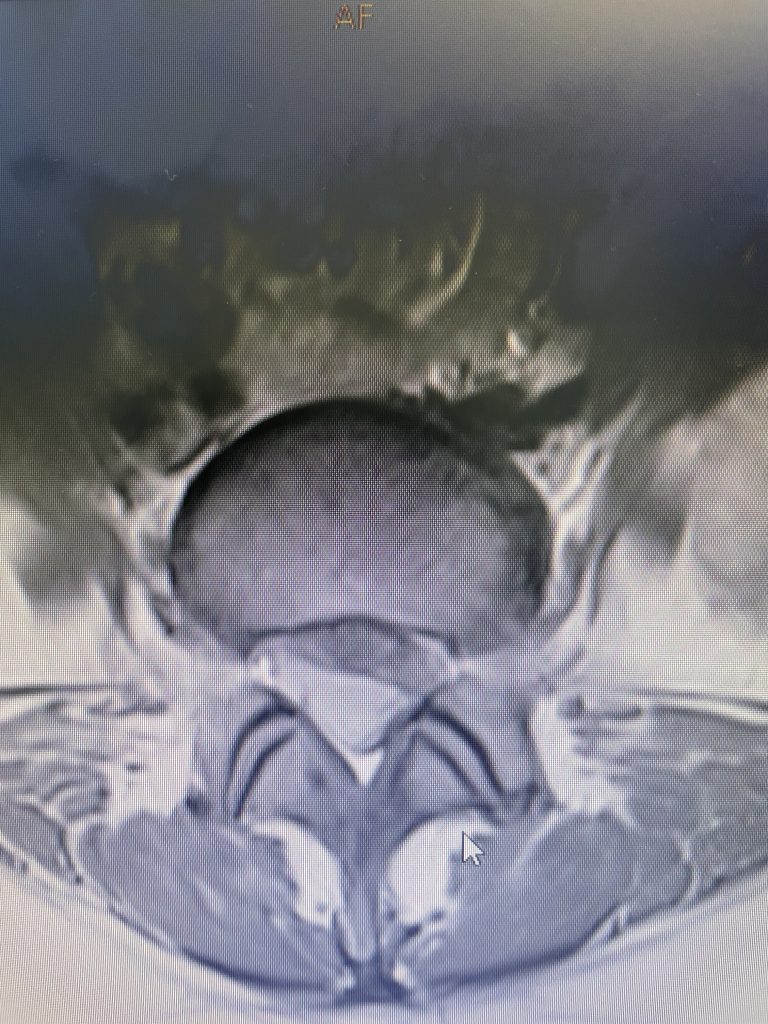

Figure 2

As a result, the patient has developed severe degenerative disc disease with collapse and a retrolisthesis above. There is also a left sided disc osteophyte complex that is causing foraminal stenosis and mild thecal sac compression. Up to this point, the patient had failed all means of conservative management including physical therapy, epidural injections, and medicine. Because of the current worsening of left leg pain another MRI was performed which demonstrated a significant increase in the disc herniation with severe thecal sac compression and nerve root compression (Fig 2). It was decided to schedule the patient for decompression, discectomy, and fusion because of the progression of disc herniation and retrolisthesis.